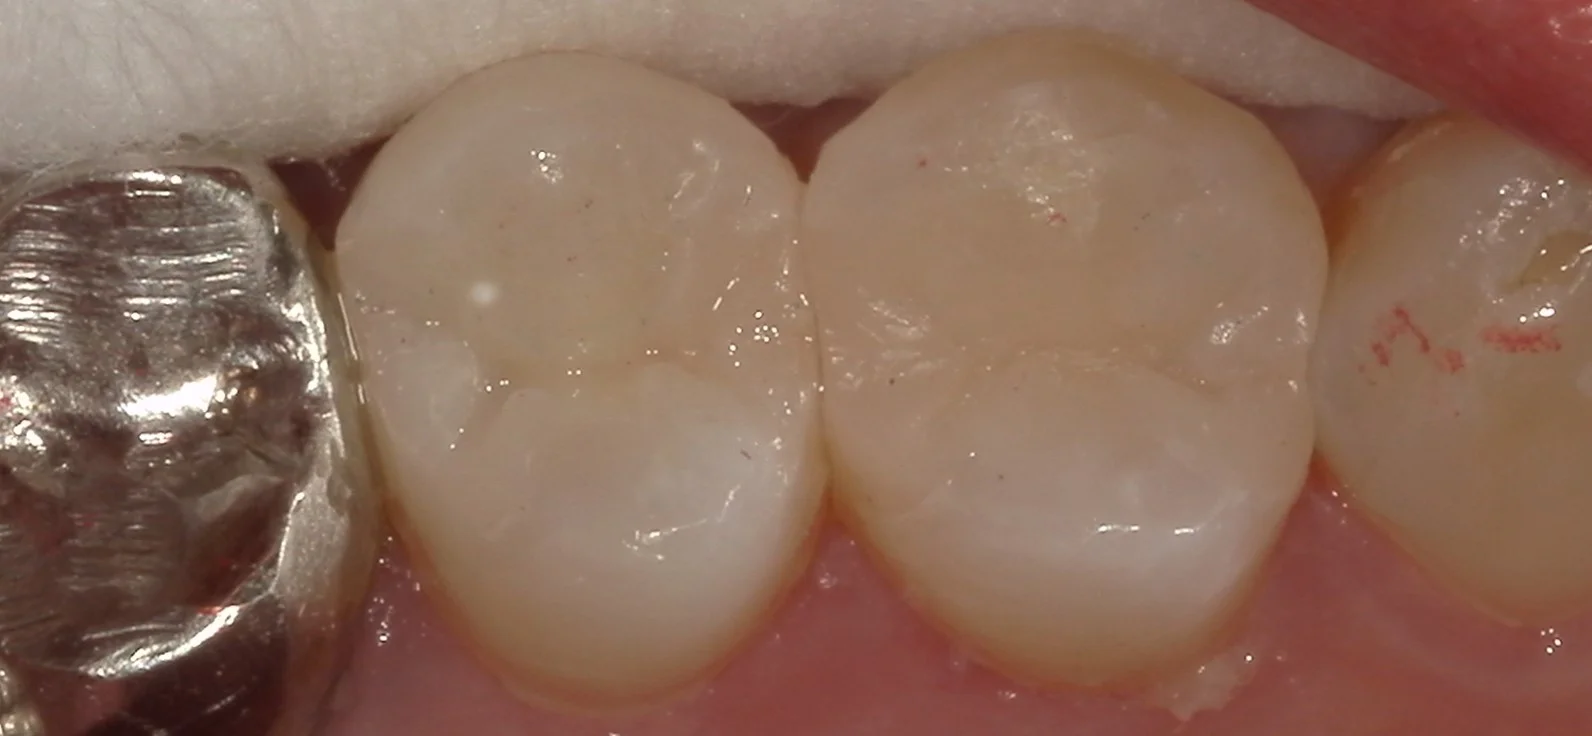

古い詰め物も全て取りきったのがこちらになります。

画面右側の歯には着色が一層残っていますが、ここは虫歯ではなく、ただ色がついているだけの層になります。

この部分は残すと接着力が落ちてしまうので、可及的に除去するようにしていますが・・・

今回はここを除去すると神経を抜く羽目になりそうだったので、温存しています。

で、詰め終わったのがこちらです。

適合は問題なく出来たので、順調に行けばしっかりと持ってくれるはずです。

ただ、残っている健康な歯の量的に次虫歯になったら被せ物になってしまうかもしれませんね(-_-;)

なるべく長い間持たせてくれると嬉しいですねぇ。